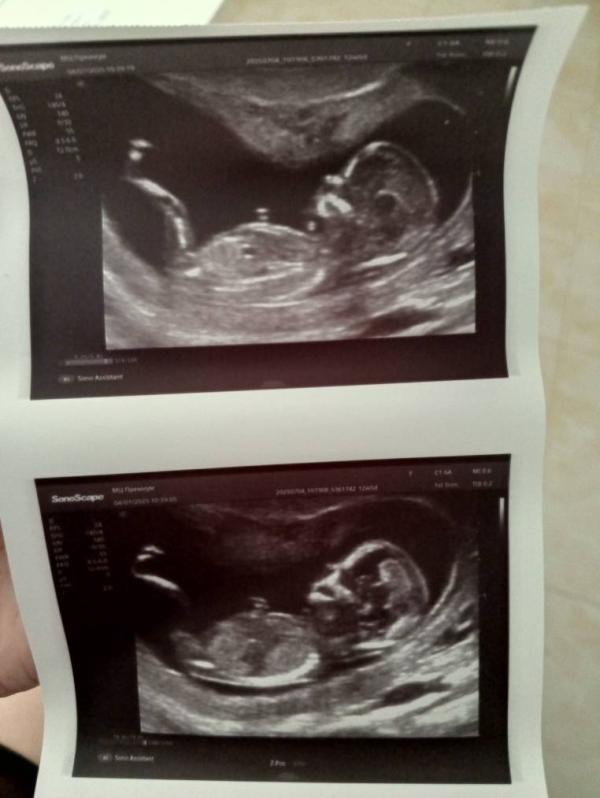

Прошла первый скрининг

По узи ребёнок здоровый, результат крови будет через 4 дня

Пол предполагать врач не стала 😅

Поставила 13 недель.